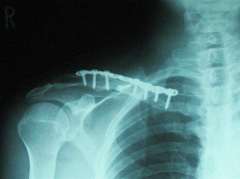

今回は先生に許可をもらってレントゲン映像をカメラで撮らせてもらいました。

4月22日の正面からのレントゲン

改めてよく見てみると20ミリくらいの長さのビス状のもの8本で120mmほどのプレートと骨を留めているみたいです。

横を向いているネジは1か所飛んでいた骨を留めていると説明を受けました。

これを外すとなると結構痛そうです、、1年後に再び外す手術は全身麻酔というのはしょうがないかなという気になってきました。